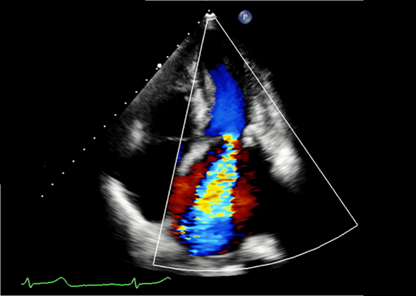

また、心臓の動きや心臓の中を流れる血液の様子(図2)などをリアルタイムで観察することで、心臓の働きを総合的に評価できるとても重要な検査です。